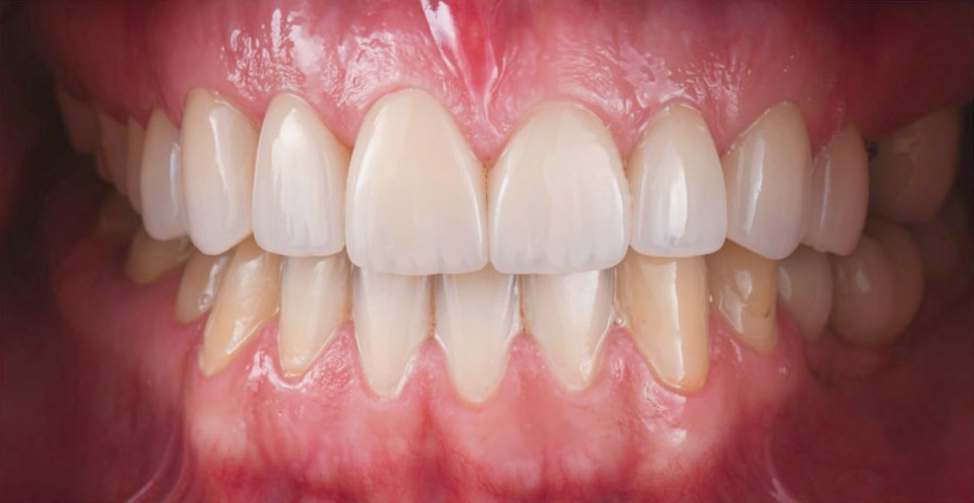

牙周病治療前、後的差別

治療前

治療後

牙齦呈現暗紅色發炎、牙齦腫大,容易

有滲出液與流血

牙齦呈現淡粉紅色、牙齦消腫不易流血